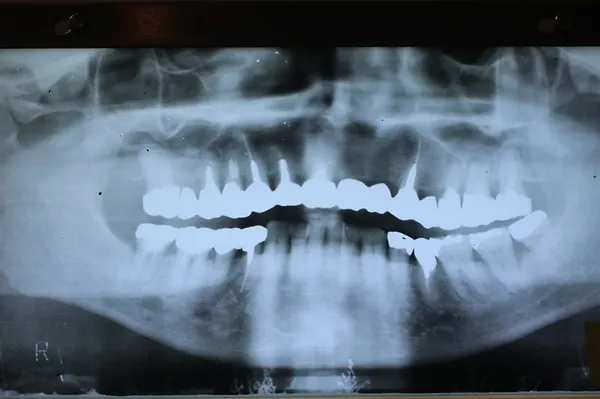

6入れ歯にしないブリッジ治療【ケース1】

H20.6.2のレントゲン

歯槽膿漏の為、上の6本の歯を抜き、上の右端から左端まで繋げたブリッジを作りました。

H31.1.25のレントゲン

H21.2.21に上の歯(ブリッジ)が完成しました。

左の写真は10年ちょっと経過したH31.1.25日に撮影した写真で、経過良好と思われます。

下顎も虫歯と歯槽膿漏のため長く持たせるために左下奥歯の一本を抜歯し残りを繋げて作りました。